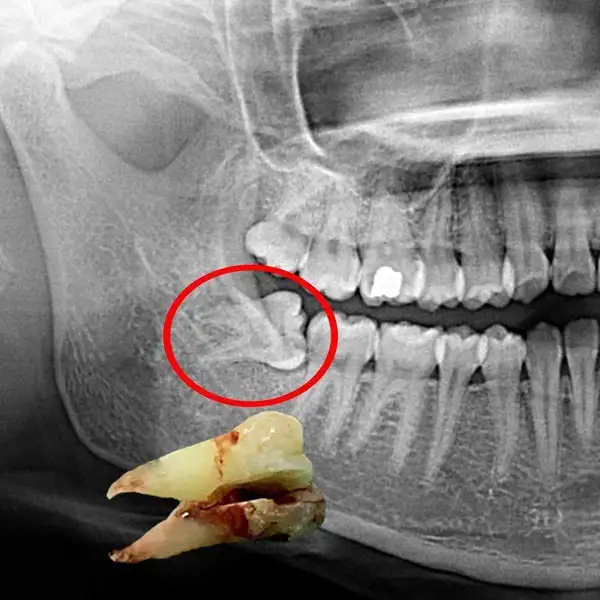

Safe and comfort-focused removal of damaged, decayed, loose, or impacted teeth using modern techniques and advanced anesthesia. Includes simple and surgical extractions such as wisdom tooth removal when required.

Our gentle approach ensures minimal discomfort during the procedure, faster healing, and smooth recovery. Detailed post-extraction care instructions are provided to promote proper healing and prevent complications, helping you return to normal activities quickly and comfortably.